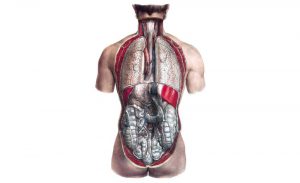

体循環の静脈系(静脈特有の走行について)

体循環にて動脈に伴行しない静脈に特有の走行については以下のものがある。

- 大動脈は1本だが、大静脈は上下2本。

大動脈は1本であるが、大静脈は上大静脈と下大静脈の2本がある。腹大動脈はほぼ正中を下行するのに対し、上大静脈、下大静脈はどちらも右側を走っている。よって左腎静脈、左腕頭静脈は右側の同静脈に比べて長くなる。 - 奇静脈系は動脈に伴行しない